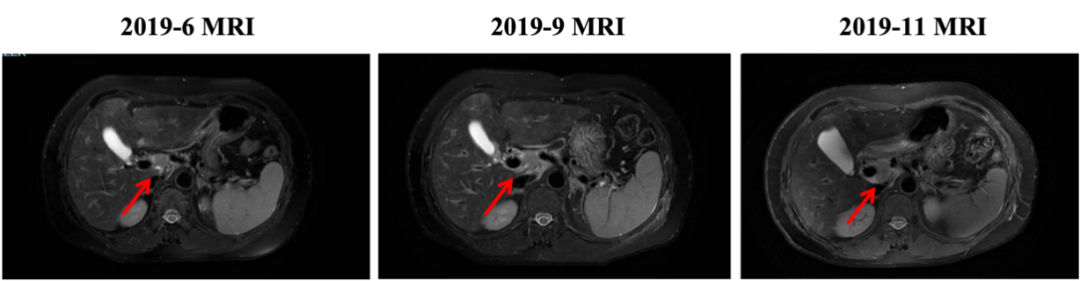

2019-11开始换用吡咯替尼联合长春瑞滨治疗,最佳评效:SD。2020-11新发肝转移病灶,评效PD,PFS为12月。不良反应:腹泻1-2级,手足麻木级(期间因不良反应予吡咯替尼减量,长春瑞滨改节拍减量)。

图5. 四线治疗